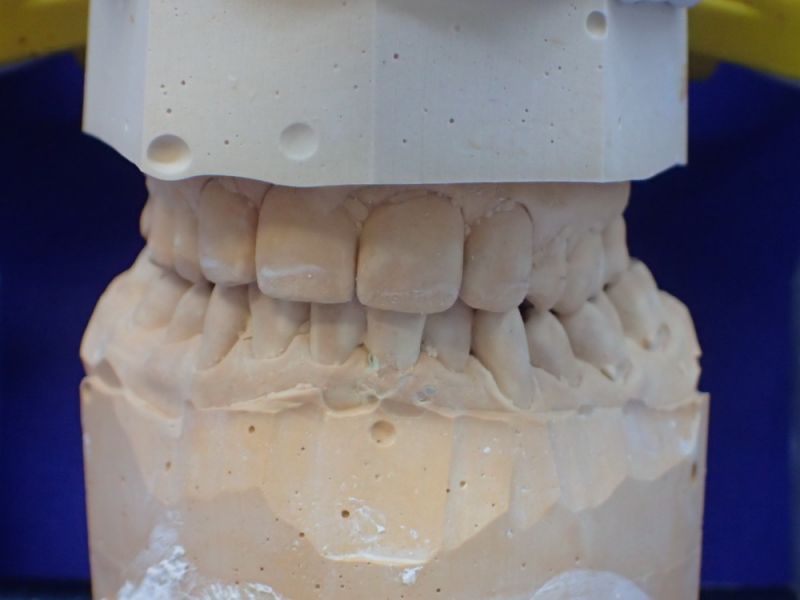

Patientin von der dänischen Grenze erhält einen adjustierten Aufbissbehelf

13746